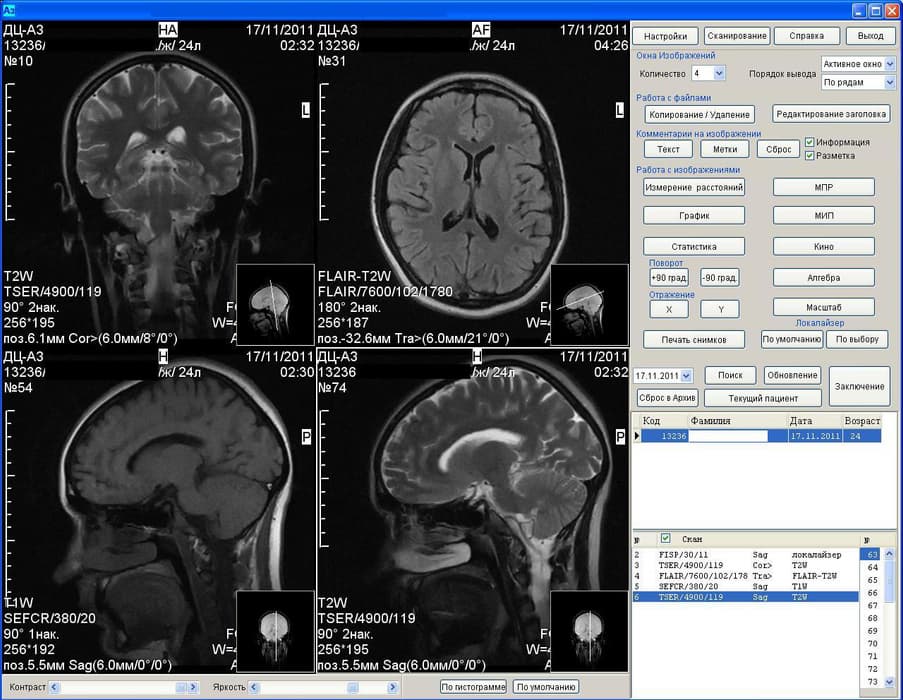

Results of the MRI machine Az-300

It is noted that scientists have restored the functional networks of the brain of healthy people and patients with depression. The technique, named the "consensus approach", revealed differences in the results of functional MRI in two groups of people.

The development of Russian scientists allows with a high degree of accuracy to determine depression. In the near future, BFU specialists plan to create a system for automatic recognition of depression using MRI.